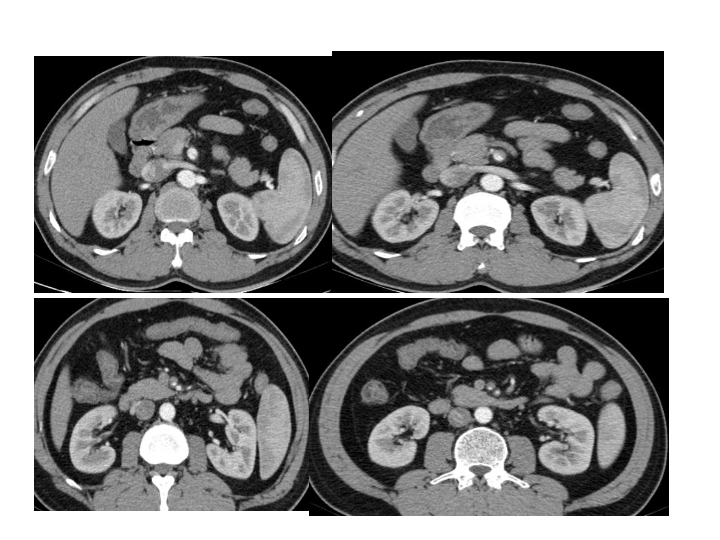

腹部外伤急救